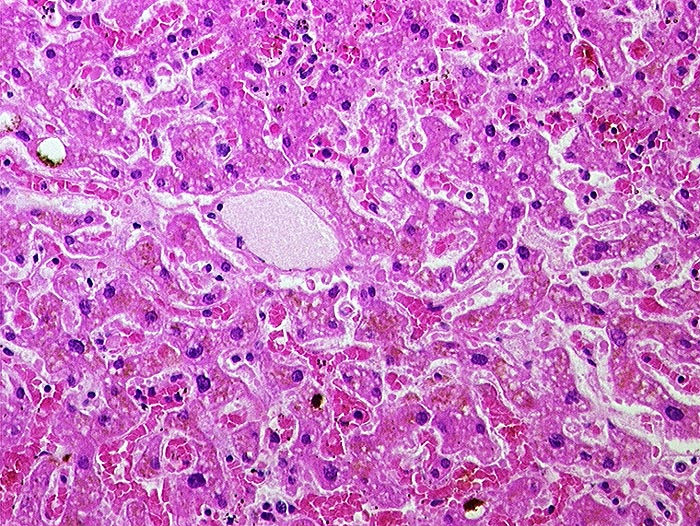

AP/ Subakute Stauung der Leber

Subakute Stauung der Leber

vaskulär / Durchblutungsstörung

Leber, Gallenwege, Pankreas

Leber

Leber HE

Normalbefund